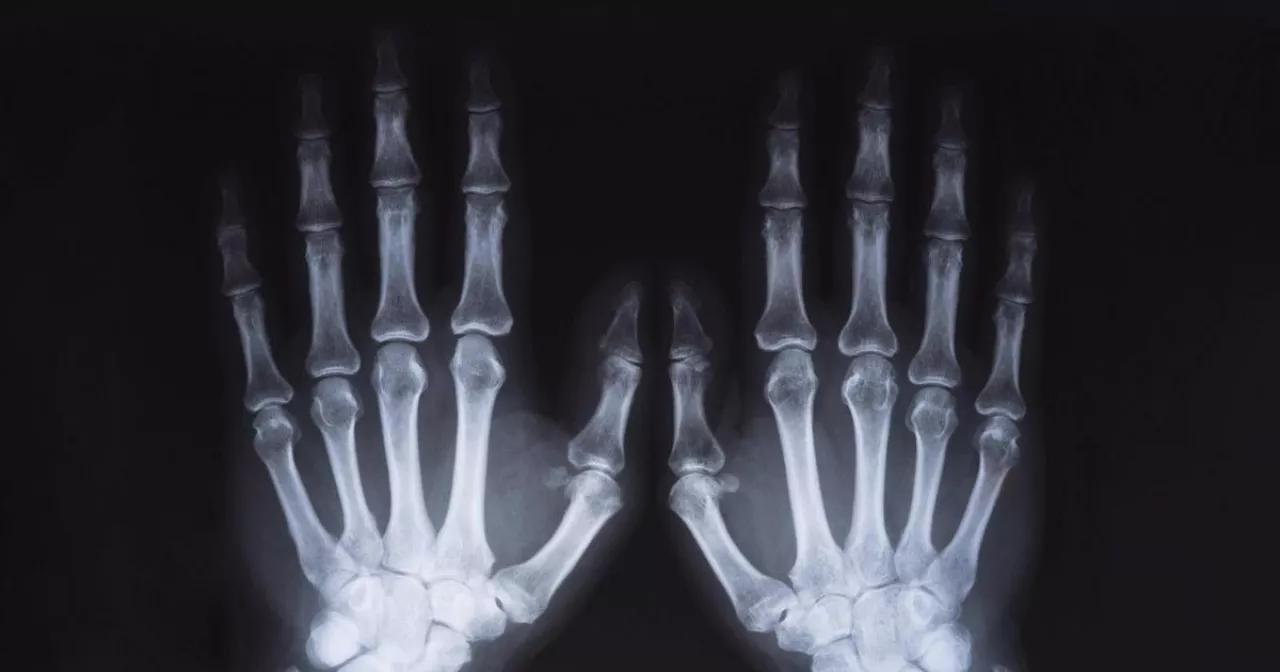

Фото: Zoonar via Legion Media

Рентген — это один из самых распространенных методов диагностики, который используют в медицине с начала XX века. Он помогает визуализировать внутренние структуры тела, выявлять травмы, диагностировать заболевания. Однако, как и любое медицинское вмешательство, проведение рентгена может сопровождаться определенными рисками. В большинстве случаев пациентам важно понимать, насколько часто можно подвергаться этому виду обследования.